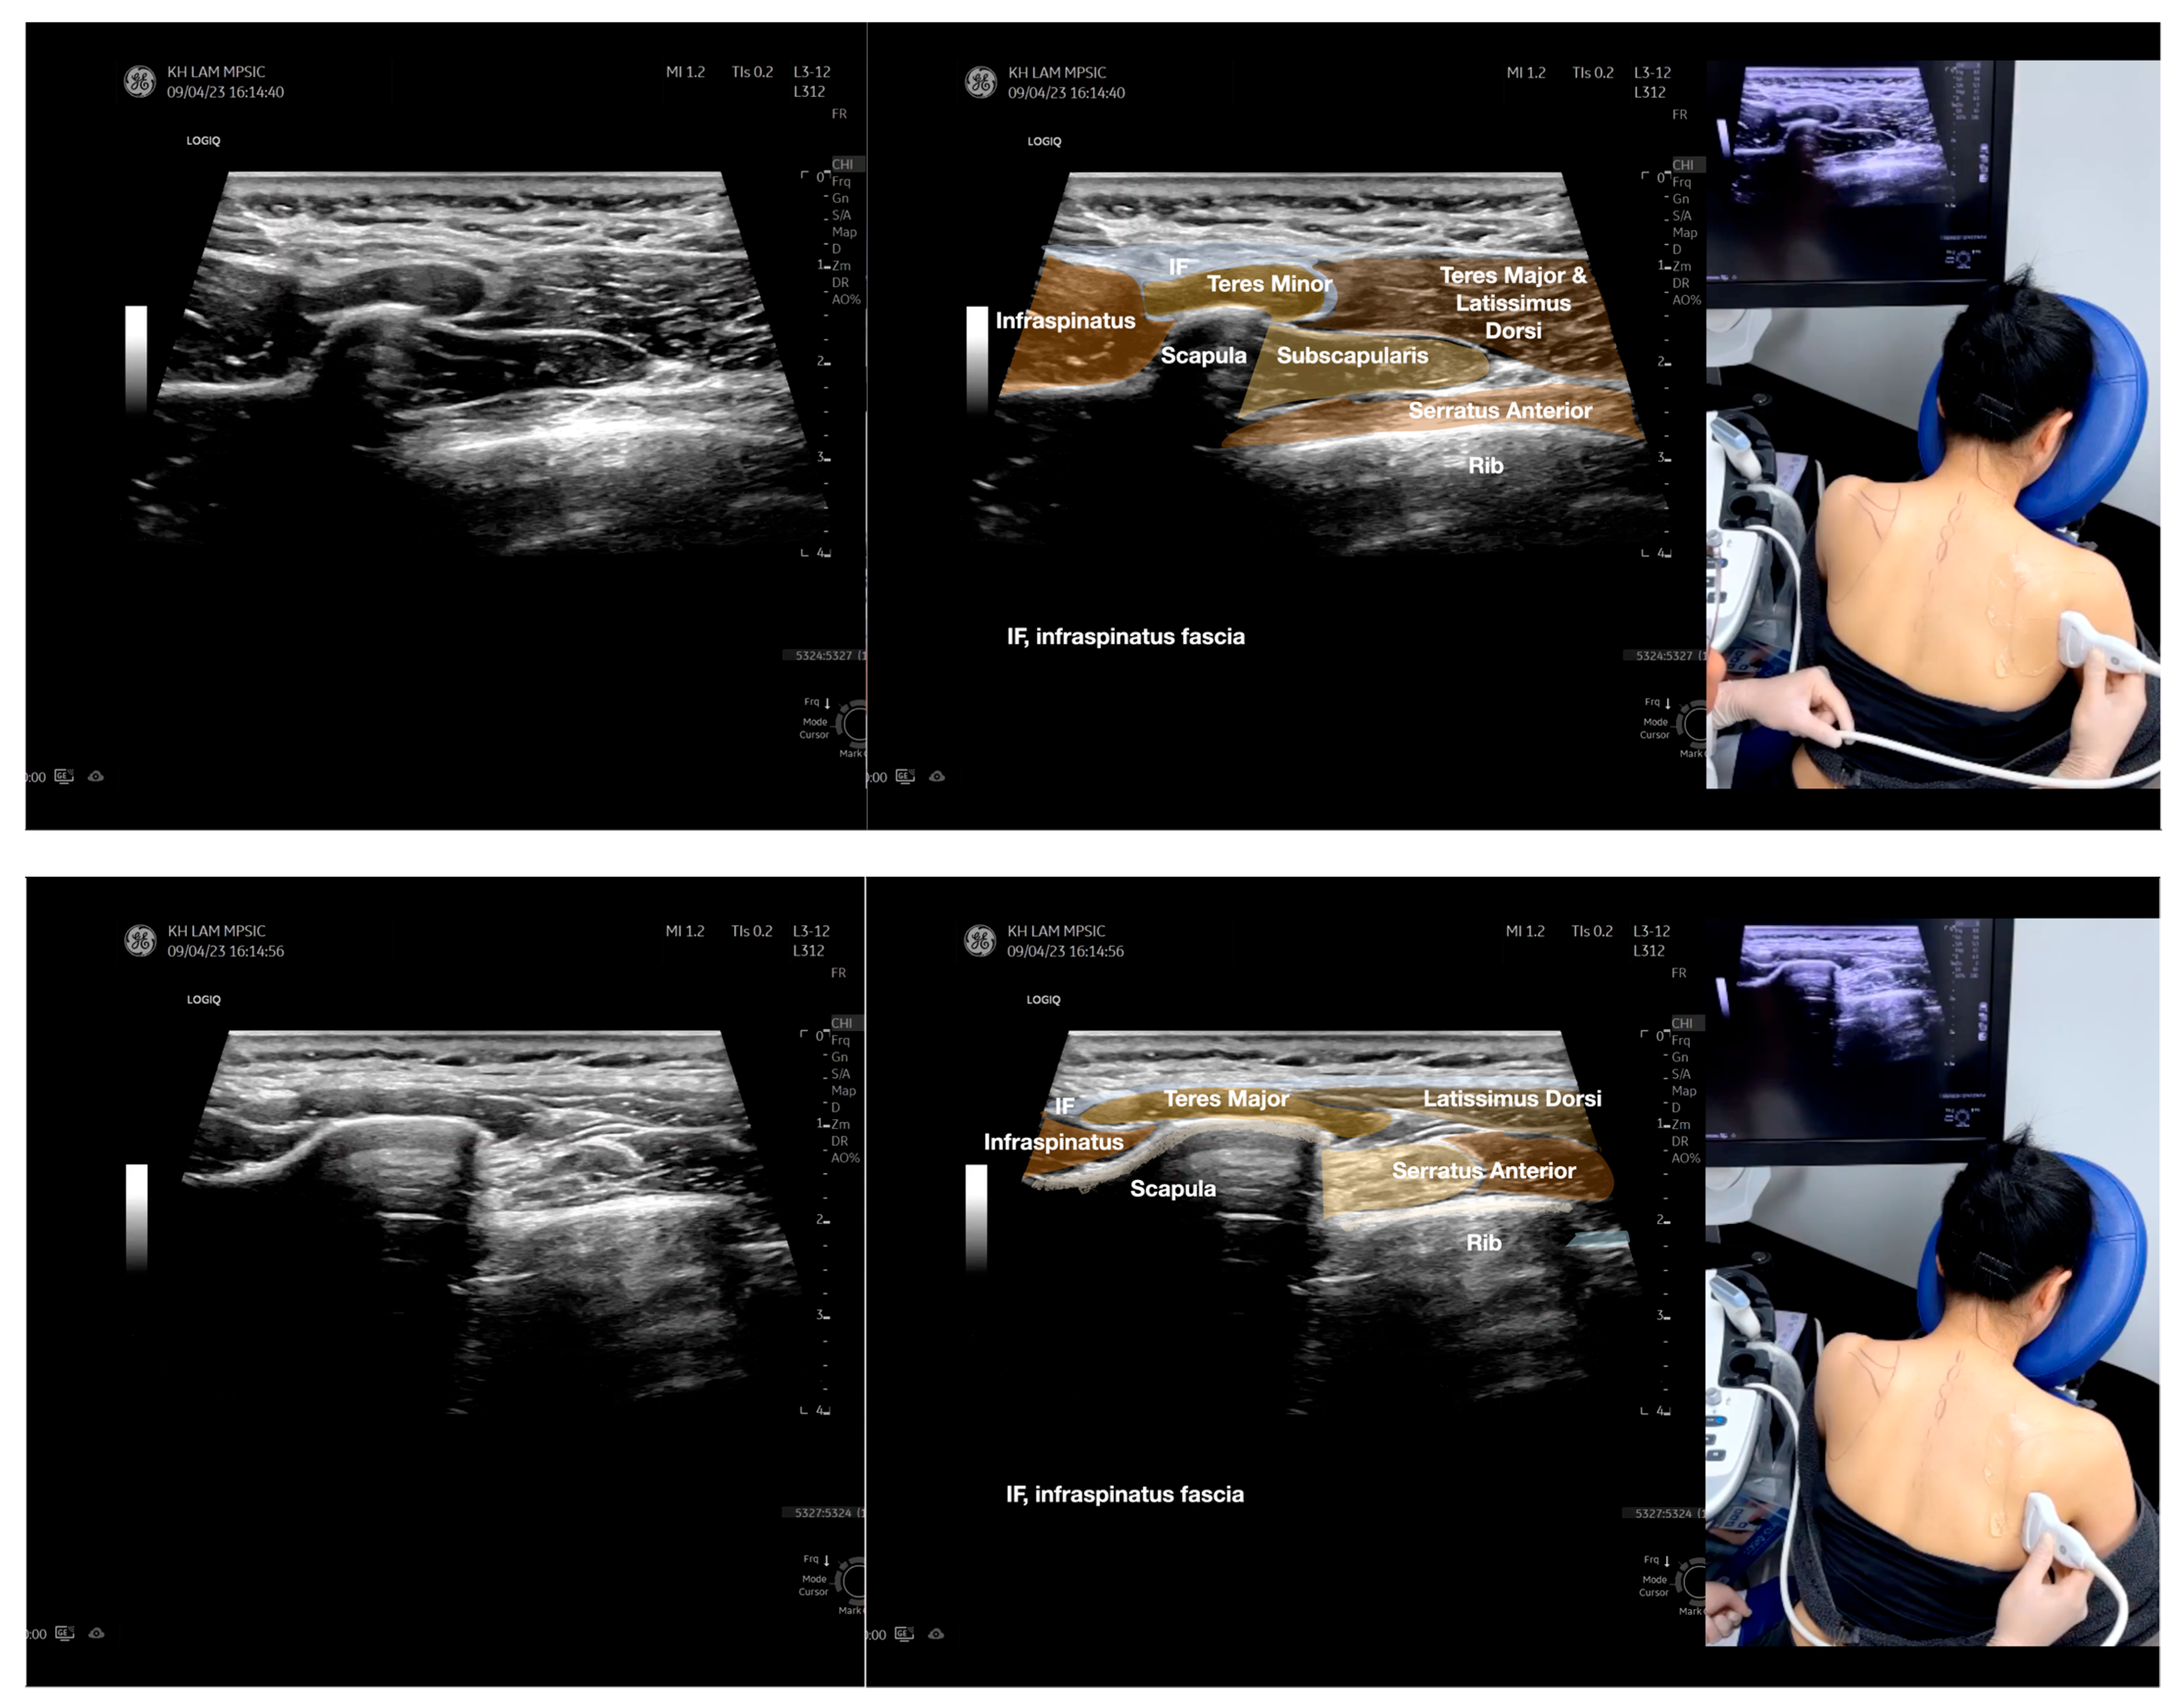

Figure 4.

Sonoanatomy of the medial edge of the scapula, its related muscles, and the infraspinatus fascia. The step-by-step scanning techniques of these structures illustrated in this figure have been shown in Video S8. Available online: https://www.dropbox.com/s/iaej3rxhl83kqt4/Figure%204.docx?dl=0 (accessed on 1 January 2023).